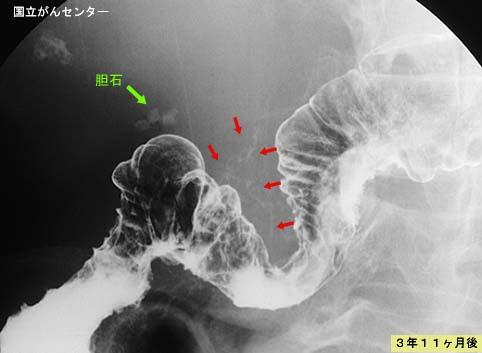

A case of phlebosclerotic colitis morphologicaly showing a progression of the lesions.

Tokyo Pref., Cooperative study between National Cancer Center and Kyushu Cancer Center

Inflammatory or ulcerative disease / lesions/phlebosclerotic colitis

Large intestine(Colon)/More than one of the above

X-ray